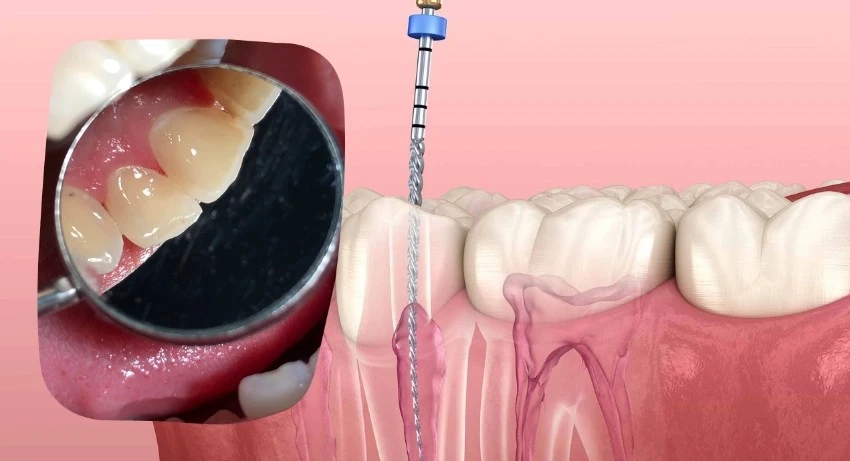

How Vitamin Deficiencies Can Impact the Color of Your Teeth

What Vitamin Deficiency Causes Yellow Teeth in Dubai